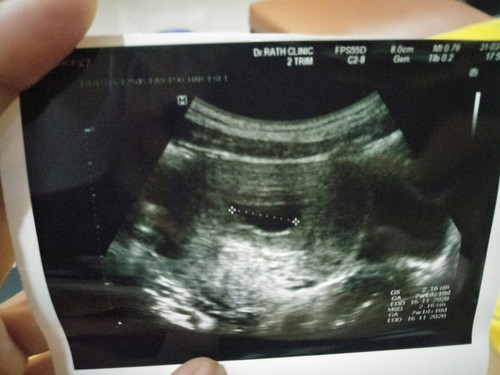

7w2d

ซาวด์เจอน้องกันตอนไหนคะ? แบบในภาพมีน้องไหมคะ